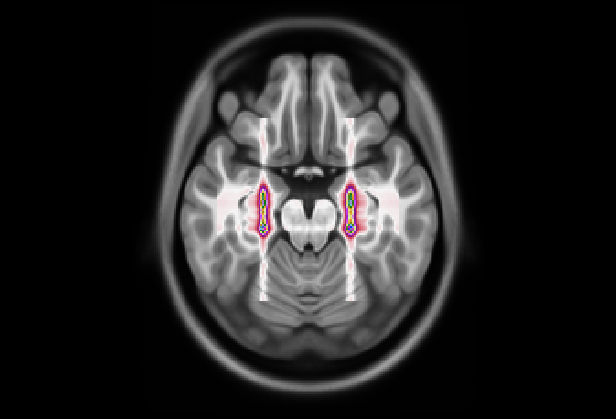

Figure 9: (Left) Visualization of mean 3D GradCAM++ map of entire dataset overlapped to MNI152 template with our model; (Right) Visualization of mean 3D GradCAM++ map of entire dataset overlapped to MNI152 template with Attention Transformer;

We also examined the interpretability of the Attention Transformer model proposed in (Altay et al., 2021). For comparison, we created 2D saliency maps using the GradCAM++ algorithm (Chattopadhay et al., 2018) across all three views and all five test sets from the different folds. These maps were combined to create a unified average 3D saliency map as outlined in Section 7. This method was also applied to generate equivalent results from the saliency maps produced using our diagnostic model. As shown in Fig. 8, the 2D maps produced by our method are generally sparser compared to those from the Attention Transformer. The method introduced in (Altay et al., 2021) employs a cross-attention mechanism via a Multi-Head. Therefore, it is plausible that the Multi-Head allows to generate 2D maps that align more meaningfully within the 3D context. This finding suggests that our approach may consider less contextual information from adjacent slices unless it is particularly relevant. In contrast, the cross-attention in the Attention Transformer might enable a more cohesive representation of the entire 3D space by considering both the local features within slices and their contextual interactions. This behavior is further clarified by creating 3D maps and overlaying them on the MNI152 template, similar to the attentional maps. As illustrated in Fig. 9 on the left, the 3D maps created using our model cover a broader and less concentrated area compared to those produced by the Attention Transformer, which are shown on the right. However, similar to the 3D attentional maps, both models predominantly focus on an area surrounding the hippocampus. As detailed in Table 9, both models identify key areas, such as the hippocampus and the amygdala, as significant. However, the emphasis on other regions varies markedly between the two. In the attention transformer model, there is a noticeable focus on the inferior lateral ventricles and the parahippocampal region, areas less emphasized by our model in this case. This result indicates that the Attention Transformer using cross-attention in combination with GradCAM can produce results similar to those obtained by our method with a 3D attentional map. As seen in Tables 8(a) and 9(b), the first four areas on which our model focused with our approach are the same as those focused on by Attention Transformer with GradCAM. In contrast, our model with GradCAM shows broader involvement with regions such as the superior and middle temporal areas, which are not as prominent in the other cases.